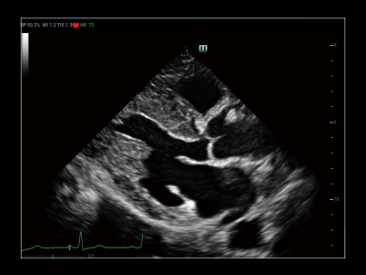

V-Flow

Векторный анализ кровотока в сосудах — это подход к оценке сосудистой гемодинамики, используя цветовой векторный анализ скорости движения и направления в каждой точке кровотока.